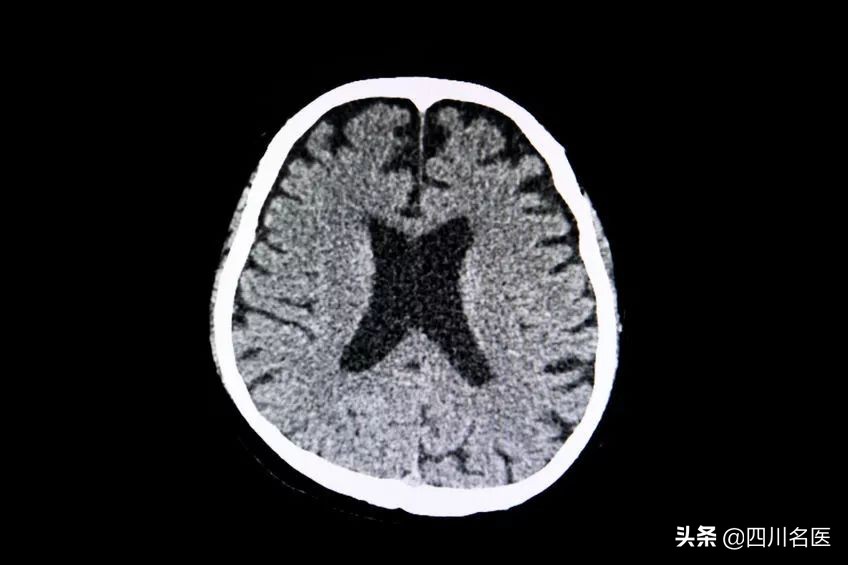

脑梗塞

异常的血脂正是导致机体动脉系统出现粥样硬化,继而引发心、脑血管疾病,出现脑梗塞以及周围血管血栓栓塞性疾病的潜在危险因素。